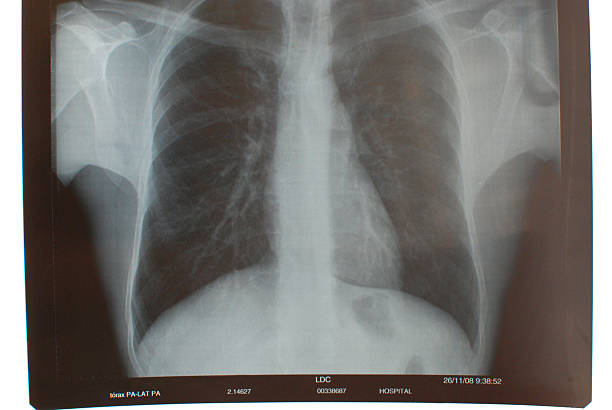

흉부 X선 검사

기흉이 의심되는 환자에게는 흉부 X선 검사를 실시하여 기흉이 있는지 확인할 수 있습니다. 이 방법은 비교적 쉽고 빠르게 기흉을 진단할 수 있습니다.